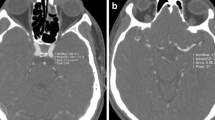

Representative cases are shown in Figs. 2, 3, and 4. Figure 2 shows the case of a 71-year-old woman with a left MCA aneurysm who underwent BSCTA under both the 120-kVp and the 80-kVp protocols after 6 months. Although the radiation and the CM doses of the 80-kVp scans were substantially lower than those in the 120-kVp protocol (CTDIvol: 14.8 vs 41.8 mGy; CM dose: 51 vs 65 ml), the image quality of the 80-kVp scan was better than that of the 120-kVp scan. Figure 3 shows the 80-kVp images of a 73-year-old woman who had undergone clipping of a right ICA aneurysm (CTDIvol: 16.4 mGy; CM: 38 ml). Arteries around the skull base and clip were obscured on the non-subtraction images. They were clearly depicted on subtraction images without severe clip-induced artifacts or confounding contrast enhancement of the cavernous sinus. Figure 4 shows the 80-kVp images of an 81-year-old woman with a clipped left MCA aneurysm (CTDIvol: 16.2 mGy; CM: 32 ml). The ICA at the level of the skull base and the aneurysm remnant at the left MCA, obscured on the non-subtraction image, were clearly depicted on the subtraction image.

A 71-year-old woman underwent bone subtraction CTA under the 120-kVp (CTDIvol: 41.8 mGy, Iopamiron 370; 65 ml) and the 80-kVp protocols (CTDIvol: 14.8 mGy, Iopamiron 370; 51 ml) at the 6-month interval. Subtraction MIP (a) and volume rendering (b) images of the 120-kVp (left) and the 80-kVp (right) protocols. Compared to the 120-kVp imaging, the 80-kVp protocol allowed for a 64.6% reduction in the radiation exposure and a 20% reduction in the amount of contrast medium while improving the arterial enhancement and overall image quality